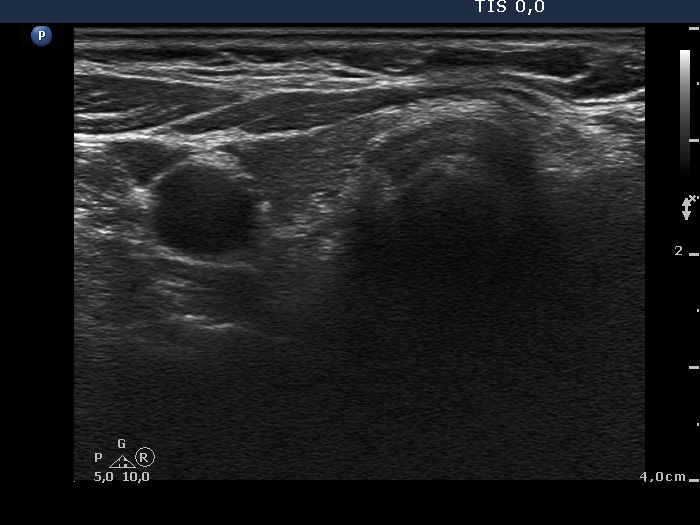

100 consecutive patients with thyroid nodule - Case 39. |

Clinical presentation: a 71-year-old woman was referred for evaluation of a slowly growing nodule known for more than 30 years. The patient had difficulties in swallowing.

Palpation: a large firm nodule in the isthmus and in the left lobe.

Ultrasonography. The thyroid was hypoechogenic. A large lesion occupied the lower 2/3 of the left lobe and the isthmus. The lesion was composed of multiple hyperechogenic areas. There was another nodule in the upper part of the left thyroid. This smaller lesion presented coarse calcification.